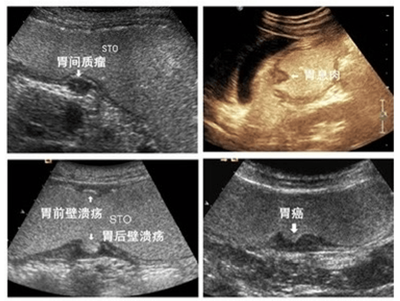

器质性病变:胃炎、胃溃疡、胃癌、胃息肉、胃囊肿、间质瘤等。

先天性病变:胃憩室、肥厚型幽门狭窄、异位胰腺、十二指肠闭锁。

其它:胃结石、胃内异物及胃底静脉曲张、食管裂孔疝等。